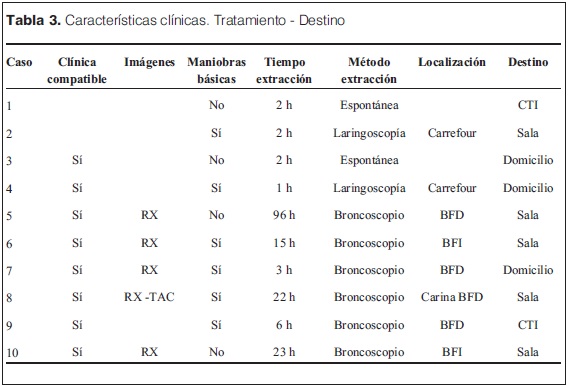

Con referencia a las características clínicas y tratamiento efectuado (tabla 3) vemos que en seis casos se efectuaron maniobras básicas para desobstruir la vía aérea, ya sea manuales (barrido de la boca con el dedo) por parte de familiares y/o personal de la salud, o la clásica maniobra de Heimlich.

La eliminación espontánea del CE se produjo en dos oportunidades (casos 1 y 3); en otros dos se extrajo al momento de la consulta en el DEP del carrefour aerodigestivo bajo sedoanalgesia (casos 2 y 4).

En seis ocasiones la extracción se realizó con broncoscopio rígido bajo anestesia general, cuatro de ellas de bronquio fuente derecho (BFD) y dos de bronquio fuente izquierdo (BFI).

Todos los CE fueron expulsados o extraídos entre dos horas y cuatro días del episodio de aspiración, con una mediana de seis horas.

No se registraron complicaciones inmediatas vinculadas al episodio ni a los procedimientos empleados para la extracción del CE.

Todos los pacientes fueron dados de alta: dos a cuidados intensivos, cinco a sala convencional y tres a domicilio desde la URE.